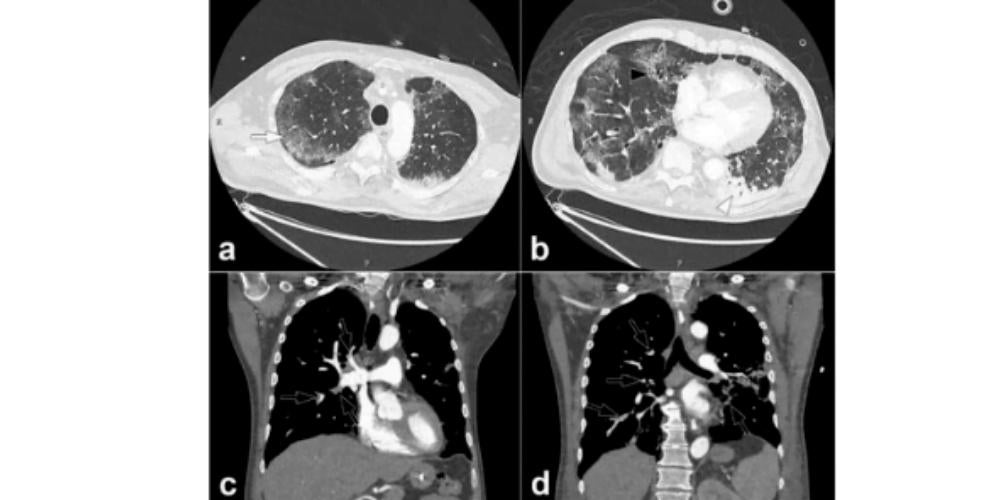

Furthermore, findings have also come to light linking COVID-19 to pulmonary embolism. In a research letter from Hôpitaux Universitaires de Strasbourg published in Radiology, the authors reported that of 106 pulmonary CT angiograms performed for COVID-19 patients over a one-month period in a tertiary care center in France, 32 patients (30%) experienced acute pulmonary embolus (PE). The rate of PE experienced by these patients was much higher than has been typically encountered in critically ill patients without the virus (1.3%), or in ER patients (3% to 10%). In this study, a D-dimer threshold of 2660 μg/L detected all patients experiencing pulmonary embolus on chest CT.

In another research letter from Centre Hospitalier Universitaire de Besancon in France, a study found that a higher proportion of COVID-19 patients had PE when contrast CT was used as the diagnostic imaging method. From symptom onset, PE was diagnosed at mean of 12 days. In addition, these patients with PE were more likely to need care in the critical care unit and be placed on mechanical ventilation.

In a case report from Cooper University Hospital in Camden, NJ, researchers described multiple areas of arterial and pulmonary thrombosis in an 84 year old male COVID-19 patient.